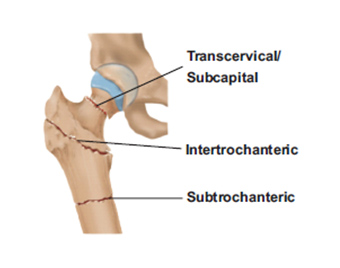

break-type-diagram

break-type-diagram

break-type-diagram

break-type-diagram